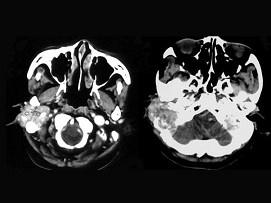

问题 女,56岁,右侧中耳术后发现右外耳道新生物一年,PE:右外耳道内段被新生物充满,CT如图所示,应诊断为 ( )

选项 A、听神经瘤 B、中耳结核 C、中耳癌 D、颈静脉球瘤 E、胆脂瘤

答案 C